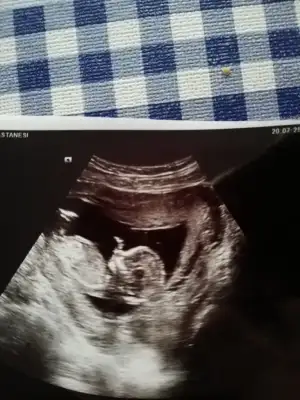

Bende erkek hissediyorum rüyamda da erkek gördüm ama doktorum kız gibi dedi bu çarşamba günü tekrar gidecem bakalım kendini gösterir inşallah

Canım rüyanda gördüğünün tersi çıkıyomuş. Bende hep kız gördüm ama doktor erkeğe benziyo dedi.